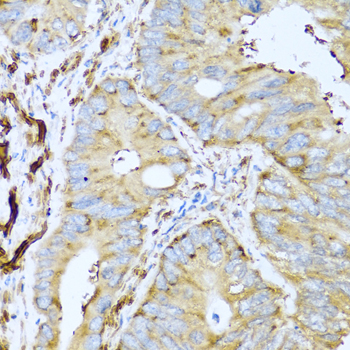

Immunohistochemistry of paraffin-embedded human liver using CSH1 antibody at dilution of 1:100 (40x lens).

,

Immunohistochemistry of paraffin-embedded human colon carcinoma using CSH1 antibody at dilution of 1:100 (40x lens).